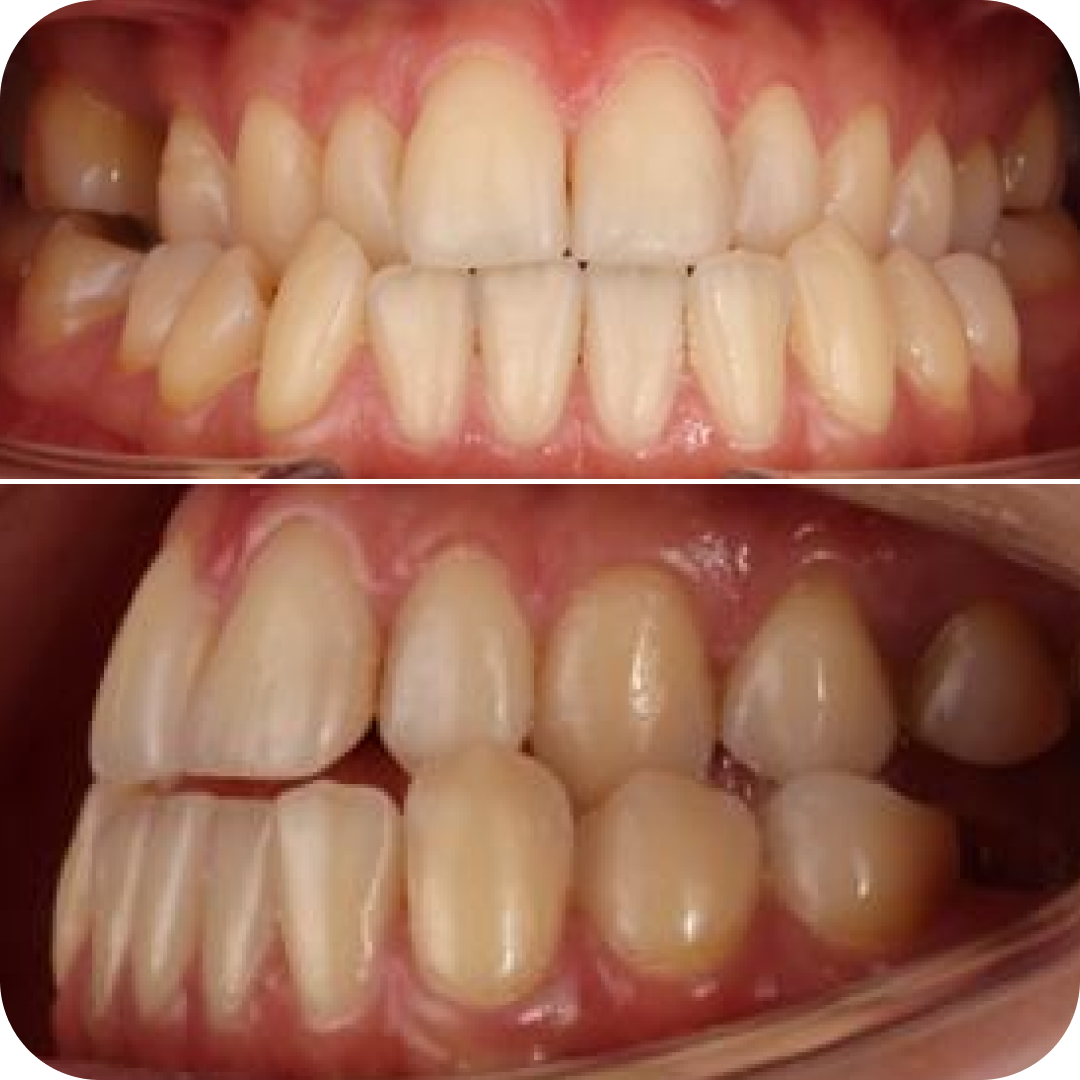

Клинический случай

🔹 Пациентка обратилась с целью стоматологической реабилитации с использованием дентальных имплантатов.

🔹 Жалобы на отсутствие зуба 1.5 и 3.6, которые были потеряны вследствие осложнения кариеса.

❗️Выявлена аномалия прикуса.

Рекомендованное лечение:

1) Коррекция прикуса с помощью ортодонтического лечения и ортогнатической операции.

2) Дентальная имплантация и протезирование.